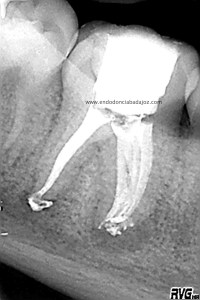

Bueno, pues hoy voy a poner un casito de otro molar inferior, un 4.6, de un chico de unos 14 años. Presentaba una necrosis con una lesión periodontal

Cuando tratamos a niños, tenemos que entender que en muchas ocasiones los conductos no se han cerrado formando sistemas de conductos muy difíciles de limpiar tanto química como mecánicamente. Es este caso, presentaba un istmo mesial acintado que lo tratamos como si tuviese varios conductos. Colocamos H de Ca, soy ,en ciertos casos, un defensor del medicamento intraconductos, con lo que lo hicimos en  dos sesiones.

Una vez que hemos limpiado los conductos con un sistema de instrumentación  Protaper en combinación con limas K3. Pasamos a obturar los mismos con una técnica de condensación vertical de ola contínua de Buchanan y un backfilling con la gutapercha inyectada de la pistola ObturaII. Tomamos varias proyecciones, orto-mesio-distal